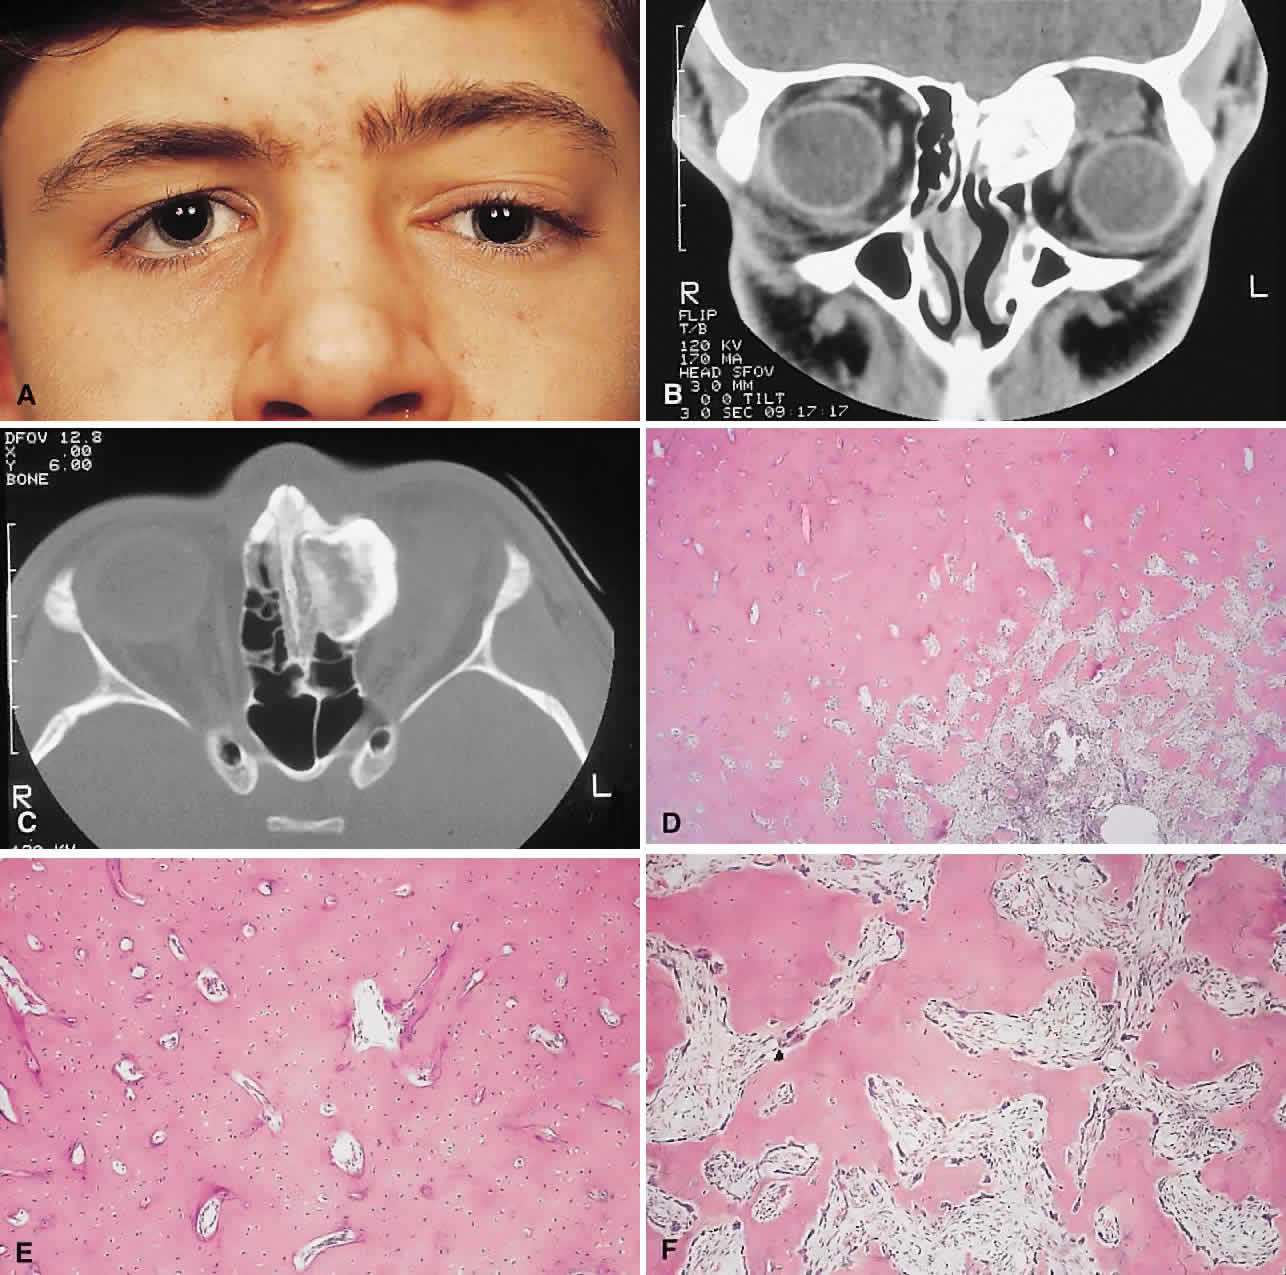

Fig. 1. A. A 15-year-old boy with a 10-month history of left proptosis had an inferolaterally displaced globe and 6 mm of proptosis. B. CT scan showed a circumscribed sclerotic mass arising from the frontoethmoidal area, with a frontal mucocele laterally. C. Bone windows revealed the bony mass to have a cancellous core and a sclerotic periphery. D. The histology showed a peripheral zone of compact bone, with increasing osteoblastic activity and fibrous tissue toward the center (hematoxylin-eosin, × 5). E and F. Higher power revealed areas of compact bone with haversian canals similar to normal cortical bone and regions of trabecular bone (F) with more osteoblastic activity present (hematoxylin-eosin, × 20).

IMAGING. The plain radiograph and CT appearances consist of an osteoblastic round or ovoid sharply circumscribed mass, usually arising in the sinus and invading the orbit. Tumors growing in a sinus conform to its internal contour and often have a bosselated surface. Osteomas may be sessile or pedunculated and generally have a diameter of 1 to 5 cm.18 Bone window settings on CT imaging often show a very dense periphery with a more cancellous internal structure. However, the relative proportions of the two densities may vary with the size of the lesion.

HISTOPATHOLOGY. It is important to distinguish osteomas from reactive osteomatous responses to infection, trauma, and chronic inflammation. The clinical and radiologic appearances are often invaluable in this regard.

Osteomas have been classified histologically into three groups depending on the predominant tissue present: compact (cortical, ivory), cancellous (trabecular, spongy), and fibrous. Fu and Perzin19 have postulated that the histologic type is partly dependent on the age of the lesion, with the compact group representing the most mature and the fibrous the least. The fibrous subtype may, in fact, be part of a continuum incorporating ossifying fibroma and fibrous dysplasia.

The compact areas resemble normal cortical bone with dense bony areas and haversian systems. However, there are subtle differences in the arrangement of the haversian canals, which is often evident to the experienced bone pathologist. The cancellous areas consist of anastomosing trabeculae with an intervening fibrovascular stroma. Fatty and hematopoietic elements may also be present in the stroma, as well as evidence of osteoblastic activity along the trabeculae. The fibrous region is made up primarily of loose fibrovascular tissue with a few irregular bony trabeculae and osteoid elements.

In our series of nine surgically treated cases, we noted that although the three types of tissue were present in varying admixtures, in all cases there was a remarkably consistent pattern of arrangement. The most peripheral zone was made up of compact bone; moving toward the center or base of the lesion, there was an intermediate zone of increased osteoblastic activity, osteoid, and vascularity. The innermost region consisted of a loose fibrous stroma with a greater number of blood vessels, few trabeculae, and many plump osteoblasts. This configuration has been described previously by Albert and associates20 and illustrates the growth of these lesions.